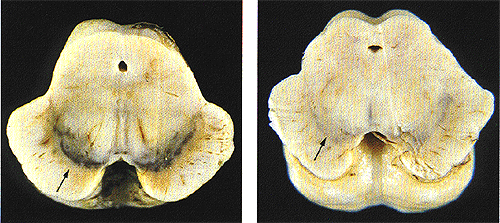

Die Symptome der Krankheit sind auf eine fortschreitende Degeneration der dopaminergen (Dopamin-ausschüttenden) Neuronen des Gehirns im Bereich der „schwarzen Substanz“ (Substantia nigra) des Mittelhirns zurückzuführen. Dadurch kommt es zu einem Mangel an Dopamin und einer Störung des empfindlichen Gleichgewichts der Botenstoffe. Makroskopisch kann dies durch ein Verblassen der Substantia nigra erkannt werden, die im gesunden Zustand durch einen hohen Eisen- und Melanin-Gehalt eine schwarze Färbung aufweist (Abbildung 3). Die Ursachen der Neuronen-Degeneration sind bis heute nicht genau bekannt. Vermutet wird eine multifaktorielle Genese, die sowohl Umwelteinflüsse als auch genetische, toxische und immunologische Faktoren miteinschließt. Bei gesunden Menschen hat die Ausschüttung des Botenstoffs Dopamin einen regulatorischen Einfluss auf Verarbeitungen des Gehirns und ist gemeinsam mit weiteren Botenstoffen an der Kontrolle der Bewegungssteuerung beteiligt. Die genaue Steuerung der Motorik und der Einfluss des Dopamins werden im Kapitel „Bewegungssteuerung“ beschrieben.